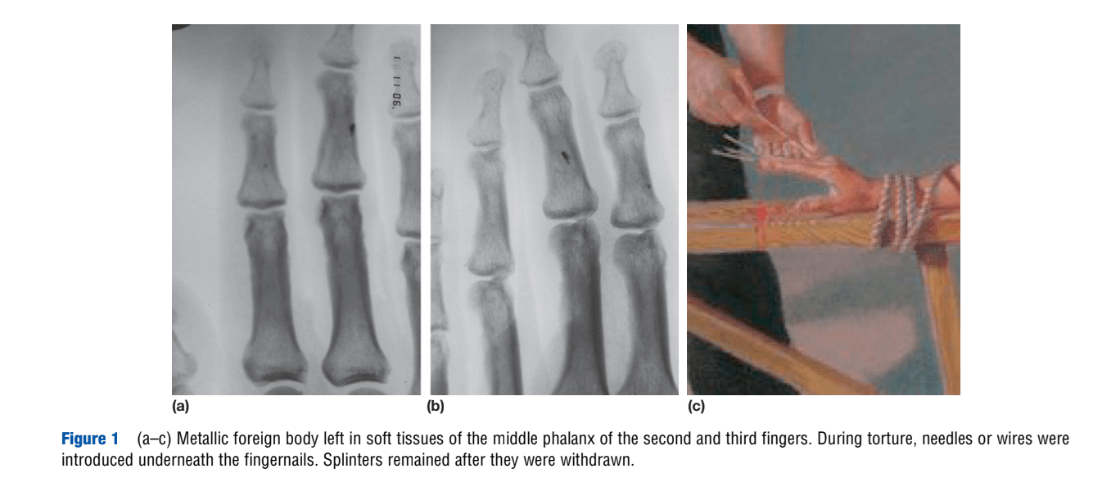

“Torture,” by H. Vogel. Encyclopedia of Forensic Sciences, second edition. 2013.